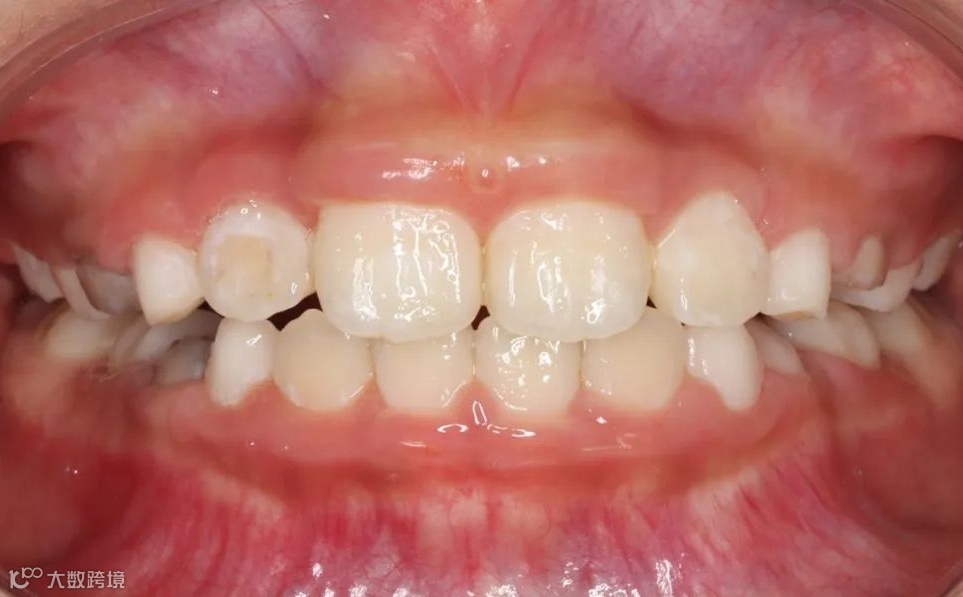

替牙期牙性反𬌗治疗前

替牙期牙性反𬌗治疗后